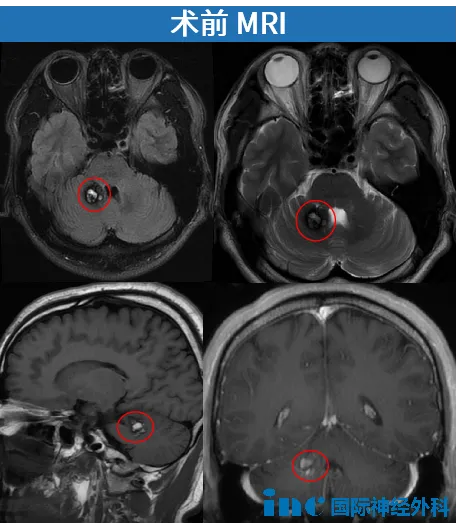

当延髓占位性病变大出血ICU这些冰冷的医学词汇,突然与自己的生命绑定,那种恐惧与无助,或许只有亲历过的人才懂。 Lisa自2009年查出患有延髓脑桥海绵状血管瘤时因为没有症状所以选择了保...